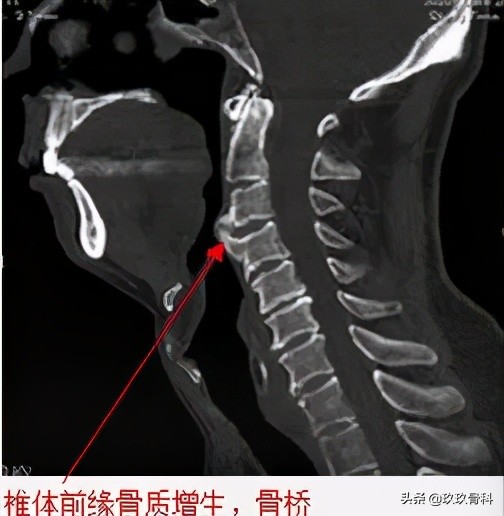

- (1) 椎体前缘骨折,常有急性外伤史,椎体后缘骨块与椎体骨质缺损相吻合,无硬化带,CT 、MRI可见周围软组织损伤征象,MRI还可发现骨水肿征象。